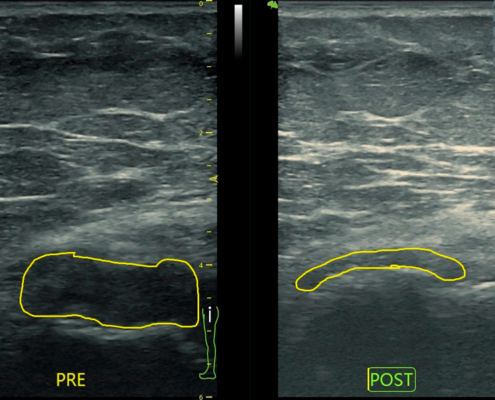

La terapia diamagnética ha revolucionado la manera en que tratamos diversas afecciones, desde lesiones deportivas hasta dolencias crónicas. En esta página, encontrarás una recopilación detallada de casos clínicos de terapia diamagnética, mostrando cómo este tratamiento innovador ha ayudado a nuestros pacientes a mejorar su calidad de vida.

Los casos clínicos de terapia diamagnética que compartimos en esta página evidencian los beneficios tangibles de este tratamiento:

- Alivio del dolor: Mejora inmediata en afecciones musculares y articulares.

- Regeneración rápida de tejidos: Favorece la curación de lesiones.

- Movimiento de líquidos